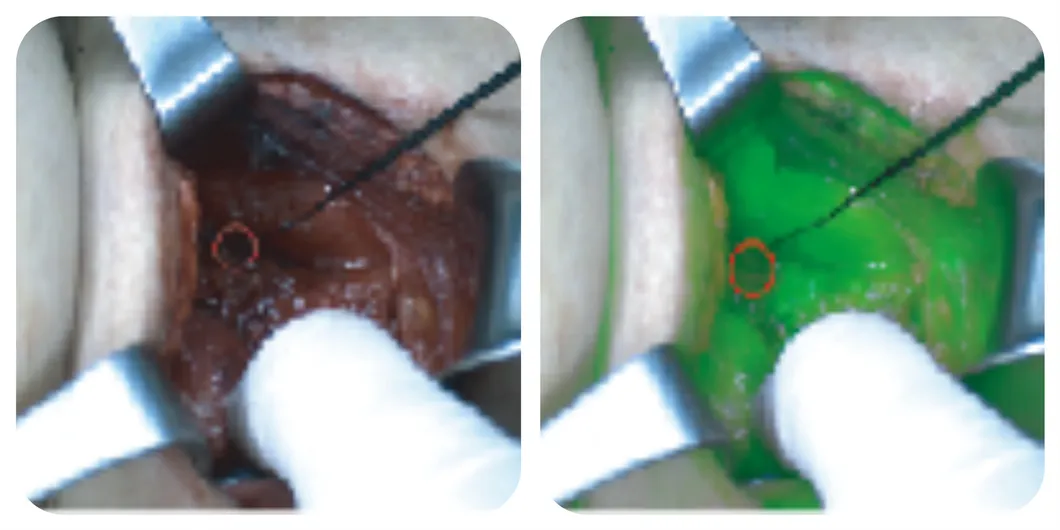

The Surgical Fluorescence Imaging System is a surgical guidance system that uses a drug-device combination approach. It employs indocyanine green (ICG) as a fluorescence probe, relying on "ultra-high sensitivity" and combining the optical properties of ICG in submillimeter-size tumors to provide surgeons with high-definition visible light, fluorescence imaging, and quantitative data for diagnostic information during tumor surgery. It is suitable for real-time observation of tissues (such as tumor tissue, margin tissue), blood supply (free skin flap), lymph nodes (sentinel lymph nodes, regional lymph nodes), and anatomical structures (liver segments, gallbladder, lung segments).

Software screenshot on the monitor

Surface light source

🏥 Precision General Surgery

Used for liver segment staining, biliary tract visualization, and real-time localization of metastases in liver, kidney, and adrenal surgeries.

Liver segment staining

Lymphatic tracing

Tumor identification

Margin determination

Biliary tract staining

Anastomotic evaluation